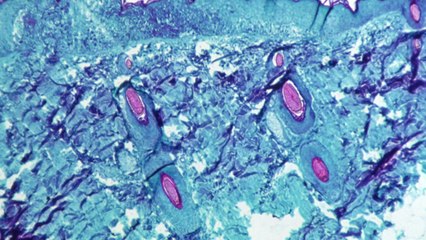

■ 전병율 前 질병관리본부장 br br br 3년 만에 발생한 메르스 확진 환자는 현재 서울대병원에서 외부와 철저히 차단된 채 격리 치료를 받고 있습니다. 이 환자와 밀접하게 접촉한 21명은 모두 자택에 격리 조치된 상태인데요. 전병율 전 질병관리본부장과 이야기 나눠보겠습니다. 안녕하세요. br br 3년 만에 또 메르스 확진환자가 나왔습니다. 일단 질병관리본부에서 메르스 대응 단계를 관심에서 주의단계로 격상을 시켰는데요. 이게 어떤 의미가 있을까요? br br [인터뷰] br 현재 메르스 단계는 크게 4단계로 구분하고 있는데요. 관심 단계라고 하는 것은 외국에서 환자가 발생했을 경우고요. 주의 단계라고 하는 것은 국내에 그 환자가 유입됐을 때 상황이고 또 경계 단계는 이제 유입된 환자로 인해서 국소적으로 환자가 확산하는 경우고. 그리고 심각 단계는 전국적으로 환자가 크게 발생하는 경우인데요. 현재 관심 단계에서 국내 환자가 유입된 상황 즉 주의 단계로 격상을 했습니다. br br br 이 메르스 환자, 다행히 위중한 상태는 아니라고 하는데요. 지금 어떤 치료를 받고 있는 겁니까? br br [인터뷰] br 이 환자는 입국 당시에는 설사 증상으로 있었고 그리고 설사 진료를 받기 위해서 삼성서울병원을 자발적으로 내원한 것으로 알려져 있죠. 진료 과정에서 이제 가래라든지 또는 발열 증상이 있는 것으로 확인이 되고 또 엑스레이 검사를 통해서 이제 폐렴 증상이 의심돼서 바로 보건당국에 의심 환자로 신고를 한 경우인데요. br br 현재 서울대학교병원 입원 중인 상황에서도 그런 발열이라든지 기침, 가래 증상으로 치료를 받고 있는 것으로 알고 있고요. 혈압 저하라든지 호흡 곤란 그런 중한 증상들은 지금 보이지 않고 있는 것으로 지금 알려져 있습니다. br br br 이번 환자도 중동지역, 쿠웨이트를 방문했다가 메르스 확진 판정이 난 건데요. 이 환자가 확진까지 이어지기까지 본인이 직접 병원을 찾았다고 하죠? br br [인터뷰] br 이 환자가 쿠웨이트에서 업무를 보고 있는 과정에서 설사 증상이 있어서 8월 28일 현지 의료기관을 방문한 것으로 알려져 있고 그리고 입국하는 과정에서 검역관에게는 설사 증상만을 신고했다고 합니다. 그리고 설사 증상에 대한 치료를 받기 위해서 본인이 스스로 리무진, 개인 리무진을 타고 가는 과정에서 삼성병원에 전화를 통해서 중동을 다녀온 사실을 이야기했고 또 그런 사실을 들은 삼성병원 의료진... (중략)br br ▶ 기사 원문 : ▶ 제보 안내 : , 모바일앱, 8585@ytn.co.